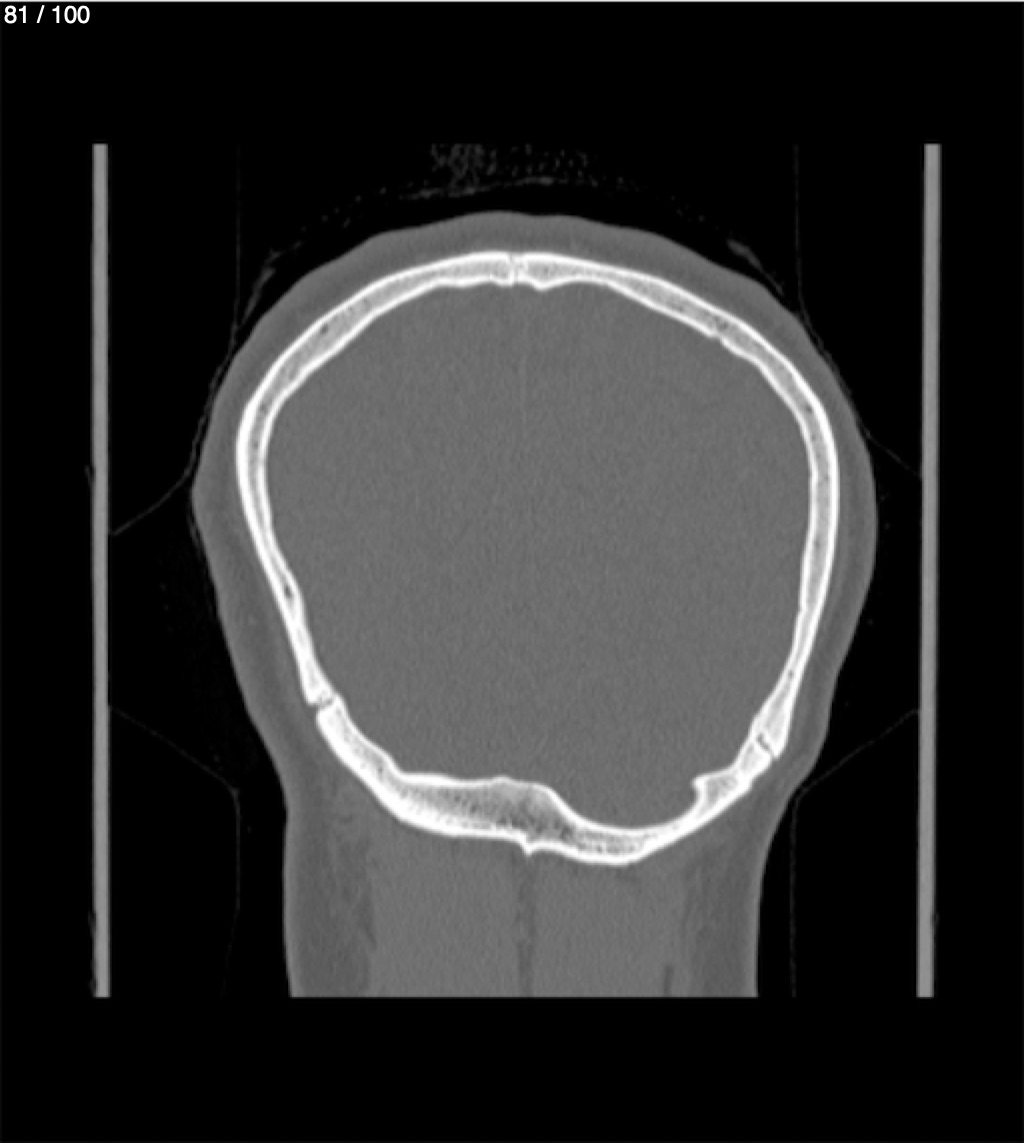

Yonelly Barrios Diaz 35A - T.C Craneo